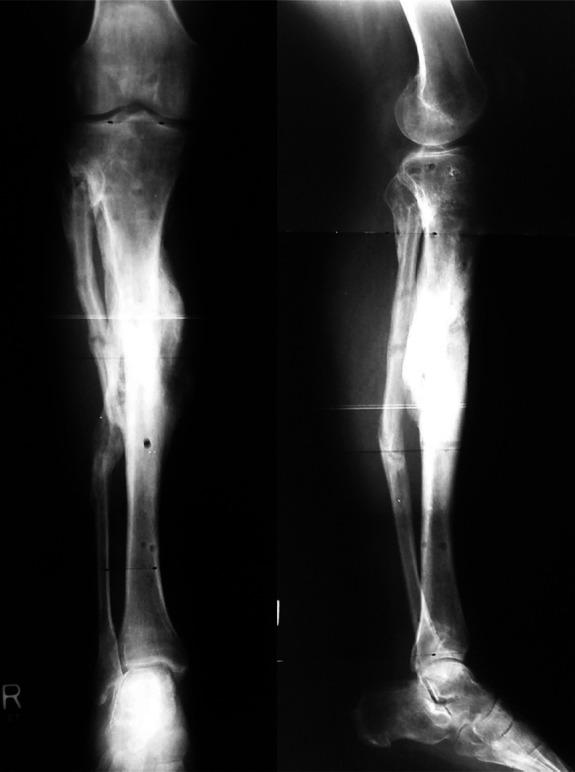

Abstract Image